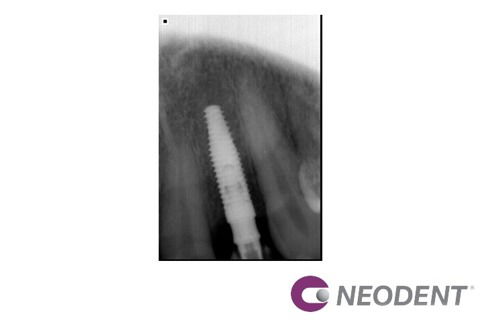

Paciente L.R.S, 53 anos, procurou o consultório devido à agenesia dos dois incisivos laterais superiores permanentes. A paciente possuía restaurações em resina composta nos laterais decíduos para reanatomizar o formato (Fotografia 1). O elemento 62 havia esfoliado e foi reabilitado através de uma ponte provisória adesiva envolvendo os dentes adjacentes. Após avaliação, decidiu-se realizar a instalação de dois implantes de maneira guiada. Através de tomografia, o caso foi planejado e a posição dos implantes foi determinada virtualmente no software coDiagnostiX® (Fotografia 2). A exodontia do elemento 52 foi realizada (Fotografias 3 e 4) seguida da instalação dos implantes Neodent Helix GM Aqua 3,5x13mm com guia restritivo (Fotografias 5 e 6). Utilizou-se componentes protéticos diferentes, munhão anatômico para lateral 1,5 de altura no elemento 12 (Fotografia 7) e munhão universal 3,3x4x2,5 de altura no elemento 22 (Fotografia 8). Os dois componentes foram instalados com torque final de 20N seguindo o conceito One abutment one time1 e as provisórias foram instaladas no mesmo dia.Aspecto radiográfico e clínico após 2 meses (Fotografias 9,10 e 11). Além de aumentar a previsibilidade do resultado, a utilização do método guiado melhora a cicatrização, já que a instalação é realizada sem incisões.